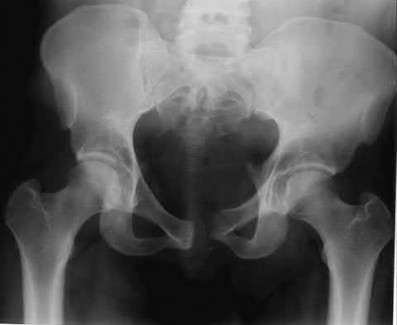

Figure C is an axial CT scan of a lateral compression type 3 (LC3) pelvic ring injury.

Classically, LC3 injuries demonstrate an ipsilateral lateral compression and a contralateral APC (windswept pelvis) fracture pattern. The most common mechanism of injury in these cases is a rollover MVC or pedestrian vs. auto. LC1 injuries are characterized by an oblique or transverse ramus fracture and ipsilateral anterior sacral ala compression fracture, while LC2 injuries consist of a rami fracture and ipsilateral posterior ilium fracture dislocation (crescent fracture). While LC1 injuries can often initially be managed conservatively with protected weight-bearing and close observation, LC2 and LC3 pelvic ring injuries are almost universally operative.

Incorrect Answers:

Answer 1: This represents a lateral compression type 2 injury. Answer 2: This represents a lateral compression type 1 injury.

Answer 4: This represents an anterior posterior compression type 2 injury. Answer 5: This represents an anterior posterior compression type 3 injury.